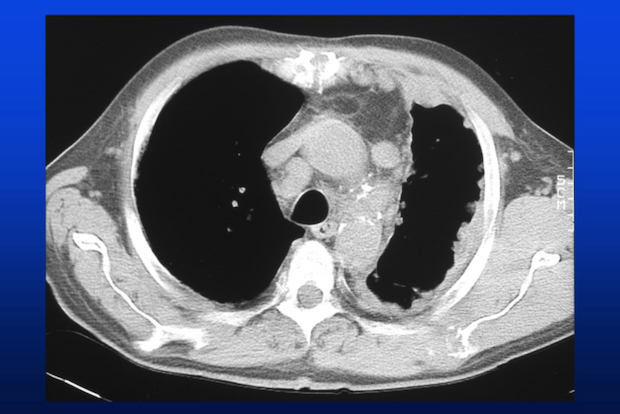

In 1998 heeft België het gebruik van asbest verboden nadat in de jaren zestig een link was aangetoond tussen asbestvezels en longziekten zoals asbestose en mesothelioom. Maar er sterven nog altijd mensen. De latentie van asbestziekten bedraagt immers > 20 jaar en die van een mesothelioom zelfs 40-50 jaar. Ondertussen is de wetgeving strenger geworden en dient asbest in openbare gebouwen en privéwoningen te worden verwijderd. Ligt de epidemische piek nu achter ons? Het verrassende antwoord van prof. Paul De Vuyst (Erasmusziekenhuis).

Asbest werd tot in de jaren negentig omwille van zijn isolerende eigenschappen gebruikt in leisteen, buizen, golfplaten, ventilatiekokers, pijpleidingen enz. Naast directe blootstelling aan asbest was er ook indirecte blootstelling via blootgestelde personen. Een dramatisch voorbeeld is dat van een gezin dat naast de fabriek van Eternit woonde. De vader, die in de fabriek werkte, de moeder en 2 kinderen die in de schaduw van de fabriek woonden, zijn gestorven in de jaren 2000. Eric Jonckheere, het laatste kind, heeft een mesothelioom. Hij is voorzitter van de Belgische vereniging van slechtoffers van asbest en auteur van het boek "Asbest".